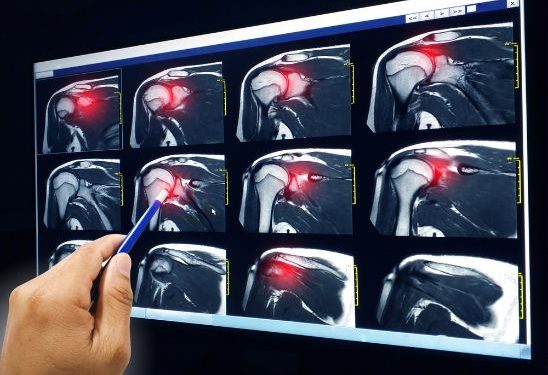

Your doctor will examine the area and ask about your past activities, work habits and other health conditions that may have contributed to the injury. Imaging tests such as X-rays and MRIs may be necessary.